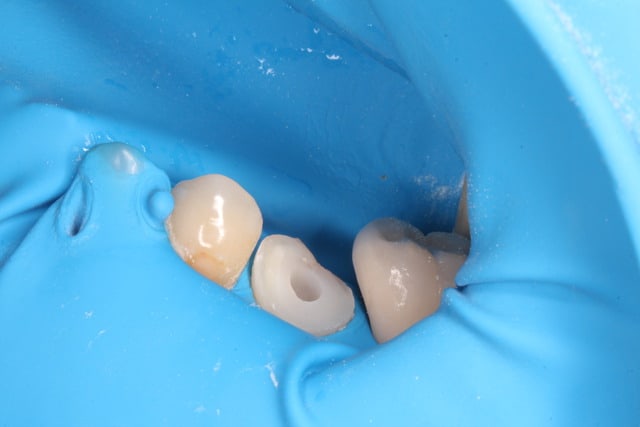

Bref je fais l'endo, et lisant de plus en plus de choses sur le sans-tenon (surtout le risque de fracture supérieur qu'il engendrait par perte de substance dentinaire) je me suis lancé dans un "Nayyar" core, compo descendant dans les entrées canalaires et par dessus une CCC.

mais il faut aller au fond de ton raisonnement , No post ok mais si possible No Crown !

pourquoi tailler la paroi distale ? le faite de réaliser un préparation périphérique te fait perdre encore de la substance, il suffite de l'abaisser de 2mm et de garder justement un paroi bien solide , pour le reste , pas besoin de nayyar core tu peux très bien coller à plat ou dans la chambre pulpaire. On obtient un mix entre l'onlay et l'endocouronne , je sais même pas comment cela s'appelle d'ailleurs !